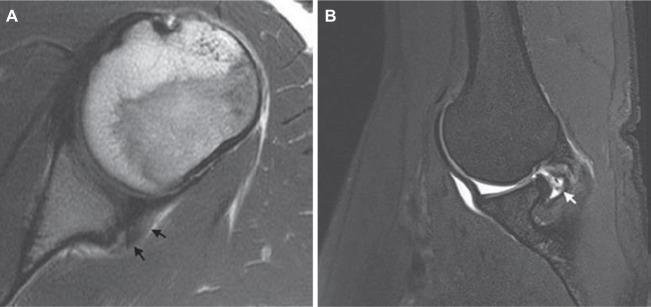

Glenohumeral internal rotation deficit (GIRD) is an adaptive process in which the throwing shoulder experiences a loss of internal rotation (IR). GIRD has most commonly been defined by a loss of >20° of IR compared to the contralateral shoulder. Total rotational motion of the shoulder is the sum of internal and external rotation and may be more important than the absolute value of IR loss. Pathologic GIRD has been defined as a loss of IR combined with a loss of total rotational motion. The leading pathologic process in GIRD is posterior capsular and rotator-cuff tightness, due to the repetitive cocking that occurs with the overhead throwing motion. GIRD has been associated with numerous pathologic conditions, including posterior superior labral tears, partial articular-sided rotator-cuff tears, and superior labral anterior-to-posterior tears. The mainstay of treatment for patients with GIRD is posterior capsular stretching and strengthening to improve scapular mechanics. In patients who fail nonoperative therapy, shoulder arthroscopy can be performed. Arthroscopic surgery in the high-level throwing athlete should be to restore them to their functional baseline with the minimum amount of intervention possible.

肩肱关节内旋不足(GIRD)是一种适应性过程,在此过程中,投掷肩的内旋(IR)会出现丧失。GIRD最常见的定义是与对侧肩相比,内旋丧失超过20°。肩部的总旋转运动是内旋和外旋的总和,可能比内旋丧失的绝对值更重要。病理性GIRD被定义为内旋丧失合并总旋转运动丧失。GIRD的主要病理过程是后关节囊和肩袖紧张,这是由于过头投掷动作中反复出现的上举动作所致。GIRD与多种病理状况相关,包括后上盂唇撕裂、部分关节面侧肩袖撕裂以及上盂唇从前到后的撕裂。GIRD患者的主要治疗方法是后关节囊拉伸和强化,以改善肩胛力学。对于非手术治疗失败的患者,可以进行肩关节镜检查。对于高水平投掷运动员,关节镜手术应尽可能以最少的干预将他们恢复到功能基线。